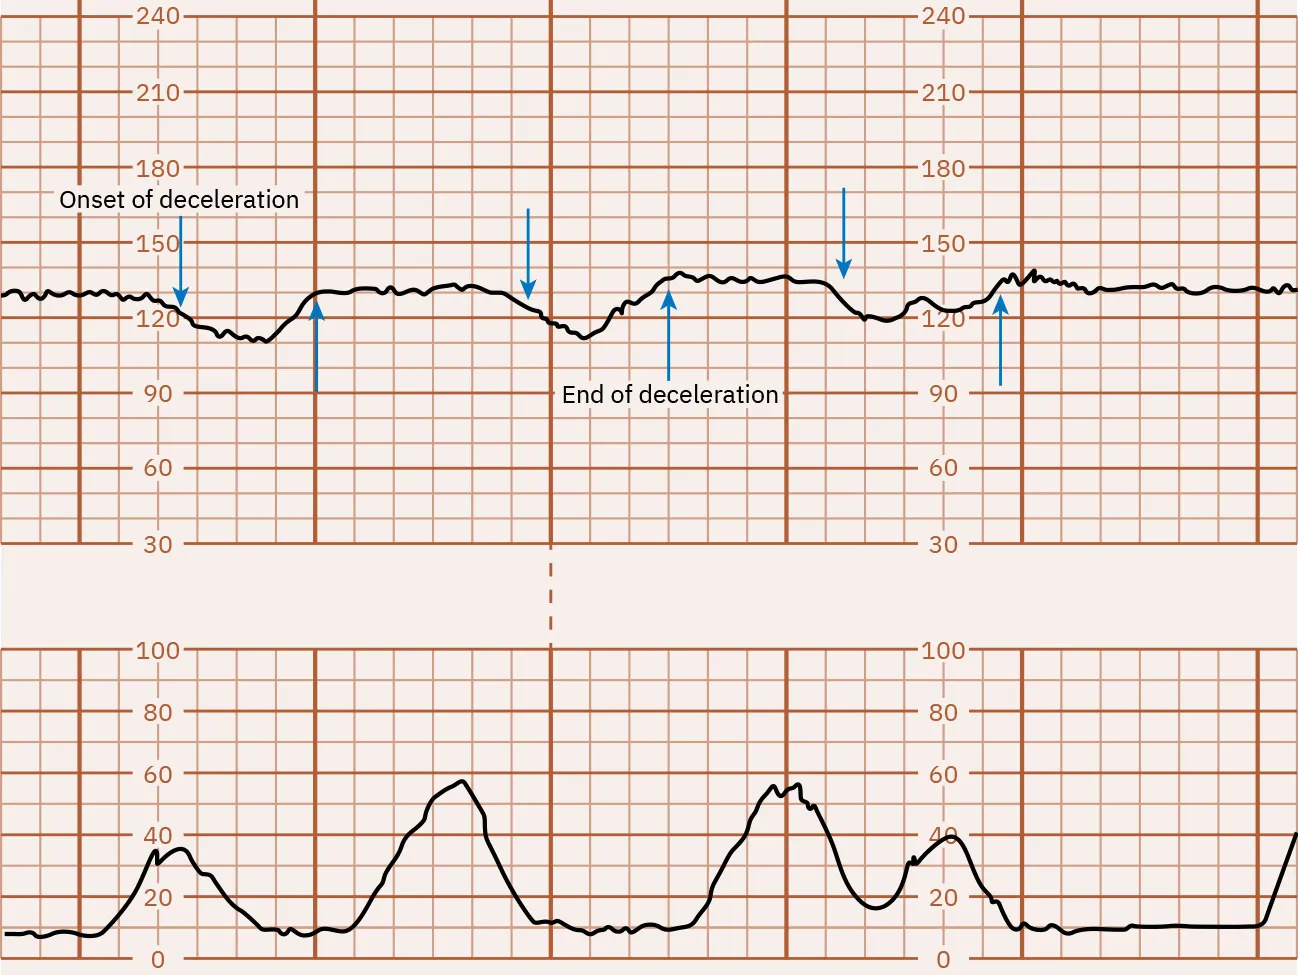

Abrupt decelerations of the FHR of at least 15 bpm below the baseline that last at least 15 to 30 seconds are called variable decelerations. They do not typically appear in a pattern and vary in onset, depth, and duration. Variable decelerations are caused by compression of the umbilical cord. Cord compression can be caused by a fetal body part squeezing the cord against the wall of the uterus during a uterine contraction or movement related to the pregnant person or fetus. Because of this, the nurse will notice that variable decelerations may or may not occur in conjunction with uterine contractions. Variable decelerations may lead to fetal hypoxia, especially when they are repetitive for a prolonged period. Figure 16.13 shows a monitor tracing with an example of variable decelerations.

Fetal heart rate reading indicating variable decelerations.

Figure 16.13 Variable FHR Decelerations Variable decelerations appear with the contractions making a โ€œVโ€ or โ€œWโ€ shape. (attribution: Copyright Rice University, OpenStax, under CC BY 4.0 license)